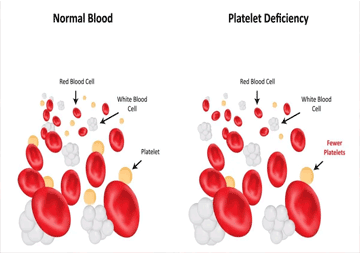

- Bluish or black spots over body, bleeding from gums or nose.